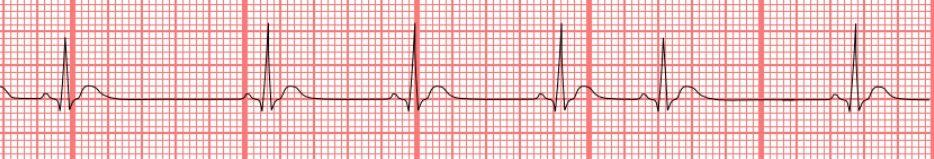

- Q1Identify.Atrial FibrillationVentricular TachycardiaNormal Sinus RhythmVentricular Fibrillation30s

- Q2Identify.Atrial FlutterNormal Sinus RhythmVentricular FibrillationAtrial Fibrillation30s

- Q3Identify.Normal Sinus RhythmAtrial FlutterAtrial FibrillationVentricular Fibrillation30s

- Q4Identify.Premature Ventricular ContractionAtrial FibrillationVentricular FibrillationPremature Atrial Contraction30s

- Q5Identify.Ventricular FibrillationPremature Ventricular ContractionPremature Atrial ContractionAtrial Fibrillation30s

- Q6Identify.Normal Sinus RhythmSinus BradycardiaVentricular TachycardiaSinus Arrhythmia30s

- Q7Identify.Sinus TachycardiaNormal Sinus RhythmSinus BradycardiaSinus Arrhythmia30s

- Q8Identify.Normal Sinus RhythmSinus TachycardiaSinus BradycardiaAtrial Flutter30s

- Q9Identify.Normal Sinus RhythmVentricular TachycardiaAtrial FibrillationVentricular Fibrillation30s

- Q10Identify.Sinus BradycardiaVentricular TachycardiaNormal Sinus RhythmAtrial Flutter30s